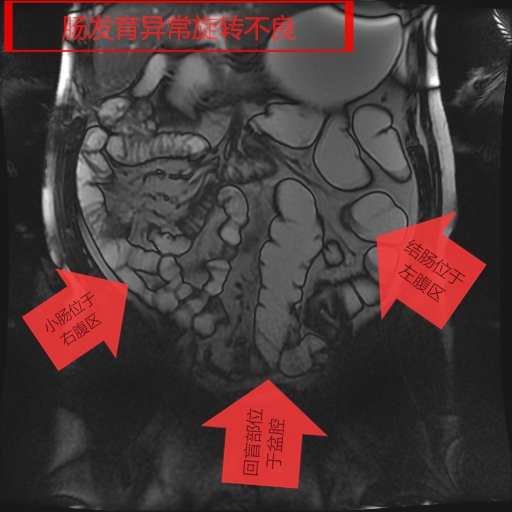

我院影像科从2018年开始,利用CT、MR分辨率高、成像方法多的特点,开展胃肠快速充盈低张CT、MR检查技术,通过多序列、多窗位、多方位检查,对肠壁、及其腔内腔外病变连续观察,取得了很好的检查诊断效果。检查技术成熟安全、无创,确诊了多例胃癌、胃息肉、结肠癌、肠先天性发育旋转不良等胃肠道疾病,并对肿瘤的转移及周围结构进行评估,为患者进一步综合治疗,打下了坚实的基础。

影像图片(一)